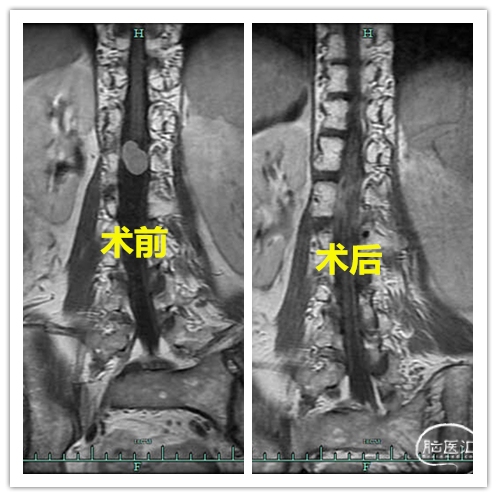

术后复查

图6. 术前后MR冠状位对比